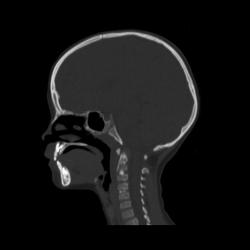

Ребенок 6 лет. Жалобы на выраженные боли в шейном отделе позвоночника. Со слов матери, боли в шее беспокоили длительное время. 2 недели отмечалась незначительная травма - девочка резко повернула голову в сторону, боли в шее услились. В настоящий момент  отмечаются выраженные боли в шее, резкое ограничение движений, повышение температуры тела, воспалительные изменения в анализах, (возможно, связанные с пиелонефритом, который также имеет место). Поступала с направительным диагнозом "ротационный подвывих атланта", однако данные рентгенографии заставили расширить круг диагностического поиска.Родовую травму мать отрицает. Хотелось бы узнать мнение уважаемых коллег.

Уважаемая коллега! С точки зрения классической рентгенологии (с учётом качества представленных снимков) могу высказать следующее:

- определяется выраженный антелистез тела С5;

- двуконтурность тел С3 и С5 может свидетельствовать о нарушении целостности костной ткани указанных тел позвонков;

- безусловно, межпозвонковые диски "поехали".

Вижу ещё раздвоенный axis.

Аксис не раздвоен, это нормальная картина для шести лет, просто верхушка зуба еще хрящевая.

Спасибо. Буду знать. По заданной теме: не хотелось бы быть освистанным, но смею предположить ювенильный ревматоидный артрит.

Случай помню. Закончилось все на удивление просто - после недели вытяжения петлей Глиссона боли ушли, движения в ШОП восстановились в полном объёме. Рентгенологические данные расценили как врожденную аномалию развития. Воспалительные изменения в анализах - как проявления пиелонефрита. В любом случае, из нашего поля зрения ребёнок ушел к нефрологам.